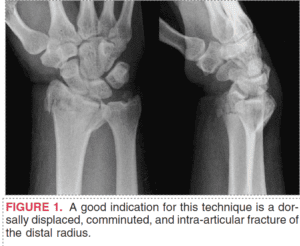

Embark on an illuminating journey through our diverse array of articles, delving into the intricate world of the wrist. Explore a wealth of information encompassing various dimensions of wrist discomfort, from unraveling its root causes to navigating through tailored treatments and preventive strategies. Our articles delve into conditions like wrist arthritis, offering expert insights and practical advice. Uncover rehabilitative exercises, ergonomic suggestions, and lifestyle modifications aimed at enhancing wrist function and reducing discomfort.